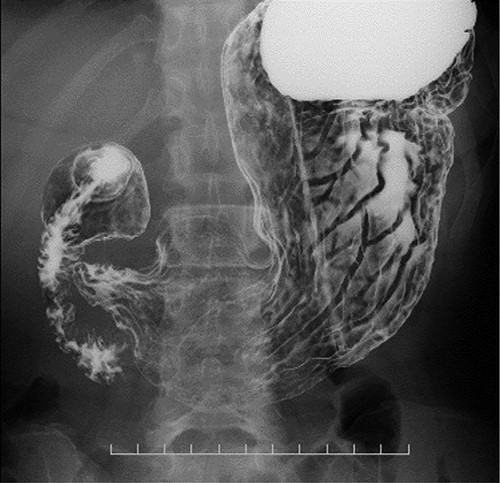

Preoperative computed tomography (CT) and barium meal studies were performed. The CT findings showed circumferential wall thickening with infiltrative change at the middle of the intrathoracic esophagus, with luminal dilation of the oral side of the stenotic esophagus (Figs 2, 3). The barium meal study showed no abnormal findings in the stomach (Fig. 4). Thoracoscopic esophagectomy was performed with the patient in the semi-prone position, followed by esophageal reconstruction using a gastric tube with the patient in the supine position. The operation was started with bilateral lung ventilation using a single-lumen endotracheal tube. A four-port thoracoscopic technique was used as follows: an observation port with a 10-mm scope was placed at the ninth intercostal space at the line of the inferior scapular angle, and two 5-mm ports and one 12-mm port for the intrathoracic procedures were placed at the third, fifth and seventh intercostal spaces, respectively, at the posterior axillary line (Fig. 5). Pneumothorax was created using 10 mmHg of CO2 to deflate the lung to achieve a better operative field. The pleura and connective tissue around the thoracic esophagus showed severe inflammatory and fibrotic changes. In particular, the middle thoracic esophagus was strongly adherent to the arch of the azygos vein and the tracheal bifurcation.

CT images showing a horizontal section of the esophagus; CT image shows circumferential wall thickening with infiltrative changes in the middle part of the thoracic esophagus.